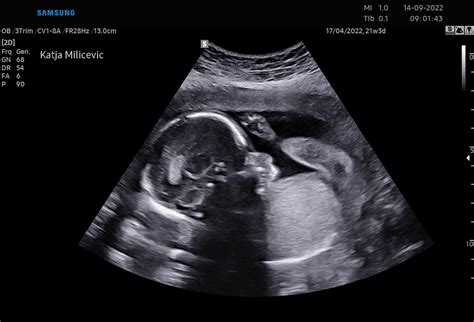

Razvoj hrbtenice je do 14. tedna nosečnosti zaključen. Ultrazvočno hrbtenico opisujemo tudi pri UZ nuhalne svetline, bolj zanesljivo pa lahko pravilen razvoj potrdimo po 16. tedna nosečnosti. Do 14. tedna nosečnosti se nosečnici svetuje preventivno jemanje folne kisline, ki pomaga preprečevati nepravilnosti v razvoju možganov in hrbtenjače.

Določanje spola: Ste se odločili, če želite vedeti, ali je otrok fantek ali punčka? Mogoče pa bi radi, da to ostane presenečenje. V tem tednu vam bo ginekolog morda že lahko povedal otrokov spol. Če spola ne želite vedeti, to ginekologu od sedaj naprej povejte pred vsakim ultrazvočnim pregledom, saj se zdaj razvijajo otrokovi specifični spolni organi. Na tej stopnji iz ultrazvoka spola sicer ni mogoče ugotoviti čisto vedno, zato ne bodite preveč razočarani, če vam ga ginekolog še ne bo mogel razkriti.